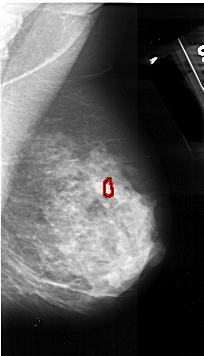

A_1029_1.RIGHT_MLO

RIGHT_MLO LINES 5326 PIXELS_PER_LINE 3046 BITS_PER_PIXEL 16 RESOLUTION 42 OVERLAY

FILE: A_1029_1.RIGHT_MLO.OVERLAY

TOTAL_ABNORMALITIES 1

ABNORMALITY 1

LESION_TYPE CALCIFICATION TYPE PLEOMORPHIC DISTRIBUTION CLUSTERED

ASSESSMENT 4

SUBTLETY 3

PATHOLOGY MALIGNANT

TOTAL_OUTLINES 1

BOUNDARY